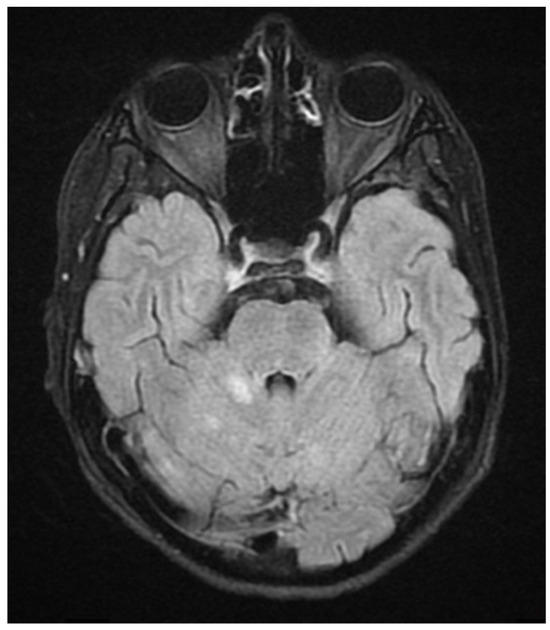

Figure 5.

FLAIR image of brain magnetic resonance imaging in the transverse plane showing a demyelinating focus in the right hemisphere of the cerebellum, including its peduncle (March 2022).

ADEM recurrence was recognized. The patient received immunoglobulins (2.0 g IV). After rehabilitation, an improvement in the neurological condition was observed over the next four weeks. The boy returned to school. Subsequently, he reported visual acuity disturbances in the left eye. Therefore, he was hospitalized in the neurology department. On admission, neurological examination showed horizontal nystagmus, lack of abduction in the right eye, dysarthric speech, and cerebellar syndrome. Brain MRI revealed numerous foci of increased signal on T2-weighted and FLAIR sequences, with the largest one occurring in the right cerebellar hemisphere accompanied by the involvement of the peduncle (Figure 5 and Figure 6) and bilateral involvement of the dentate nuclei of the cerebellum. Foci of increased signals on T2-weighted and FLAIR sequences were also found on MRI of the cervical and thoracic spine, meeting the LETM (longitudinally extensive transverse myelitis) criteria (Figure 7). Moreover, an orbital MRI showed “the left optic nerve was thickened to 3–4 mm, with increased T2 signal intensity indicating inflammation; the optic chiasm and right optic nerve were normal” (Figure 8). Again, positive serum anti-MOG antibodies were found in a clear titer of 1:100, while anti-AQP4 antibodies tested negative. Recurrent MOGAD was diagnosed based on the overall picture, and immunoglobulins were administered (a total dose of 2.0 g IV for five days). Oral azathioprine was included in the chronic treatment at a dose of 2 mg/kg body weight and oral methylprednisolone at a dose of 1 mg/kg body weight. After ten weeks (May 2022), right optic neuritis occurred during an attempt at withdrawing glucocorticosteroids. Methylprednisolone was reintroduced at a dose of 5 × 1.0 g intravenously. An MRI of the head revealed two new subcortical foci: one located in the right frontal lobe measuring 13 × 7 mm and another in the left parietal lobe measuring 19 × 14 mm (Figure 9). Additionally, the right optic nerve exhibited blurred outlines (Figure 10) and an increased signal in the central area, along with a marginally enhancing focus in the middle part of the right optic nerve measuring 2 mm in diameter. An ophthalmological consultation was conducted, revealing color vision deficiencies in the right eye across all axes, with no reading capability in the left eye. An OCT examination showed that the retinal nerve fiber layer (RNFL) in the right eye was normal (higher than a month earlier, suggesting a possible inflammatory process), while the left eye exhibited significantly reduced RNFL and ganglion cell count. Atrophy of the left optic nerve was diagnosed. Based on the clinical presentation, recurrent optic neuritis was diagnosed as a manifestation of another MOGAG, correlating with the onset of right optic neuritis following the discontinuation of methylprednisolone. Therefore, a decision was made to increase the dose of azathioprine to 2.5 mg/kg body weight and to maintain methylprednisolone for the following weeks. After the diagnosis of MOGAD with a typical radiological and clinical picture (ADEM, MDEM, recurrent ON) and the initiation of chronic immunosuppressive treatment, no more epileptic seizures were observed. It was decided to discontinue antiepileptic drugs, starting with gradual valproic acid.

Considering the criteria mentioned above, we focused on two demyelinating syndromes for differential diagnosis: multiple sclerosis and neuromyelitis optica spectrum disorder (NMOSD). To accurately diagnose demyelinating lesions, we conducted tests to detect antibodies against aquaporin-4 (AQP4) and myelin oligodendrocyte glycoprotein (anti-MOG), following the established gold standard [9]. In addition to the positive/clear titer of anti-MOG antibodies and the exclusion of antibodies against AQP4, imaging tests—resonance imaging (MRI) of the head and spinal cord—help make the diagnosis. Unlike MS, magnetic resonance imaging of the brain reveals lesions with unclear boundaries, more often located subcortically, with a characteristic cloud-like shape and a particular location in the cerebellar peduncles [1,5,10,23]. MOGAD lesions are extensive, often bilateral, and located in the thalamus and basal ganglia [1,23]. In NMOSD, brain lesions are more often located near the third ventricle [5]; the involvement of the area postrema is particularly characteristic, and the lesions usually surround the lateral ventricles [5,6].

Unlike MS, but similarly to NMOSD, in MOGAD, the demyelinating lesions in the MRI of the spinal cord are longitudinal [2], they involve more than three segments, edema is often observed, the foci are located in the central part of the spinal cord, and they produce hypointense changes in T1 images magnetic resonance imaging [1,5,23]. Demyelinating foci in the brain and spinal cord in the course of MOGAD disappear in 50–80% of cases after the relapse [1,5,10]. MRI of the orbits in MOGAD more often than in MS describes extensive involvement of the optic nerve, covering more than half of the length of the nerve [5] before the optic chiasm with contrast enhancement around the nerve [1,23] and inflammation of the soft tissues of the orbit in up to 50% of patients with ON [2]. In optic neuritis in the course of NMOSD, the optic nerve is affected mainly in the chiasm area, with involvement of the optic pathway [3] and, unlike ON, in the course of MOGAD, there is no involvement of the soft tissues of the orbit [2]. Involvement of the optic nerves in the course of MOGAD in approximately 50% may be bilateral at the same time [1,2,5,24].